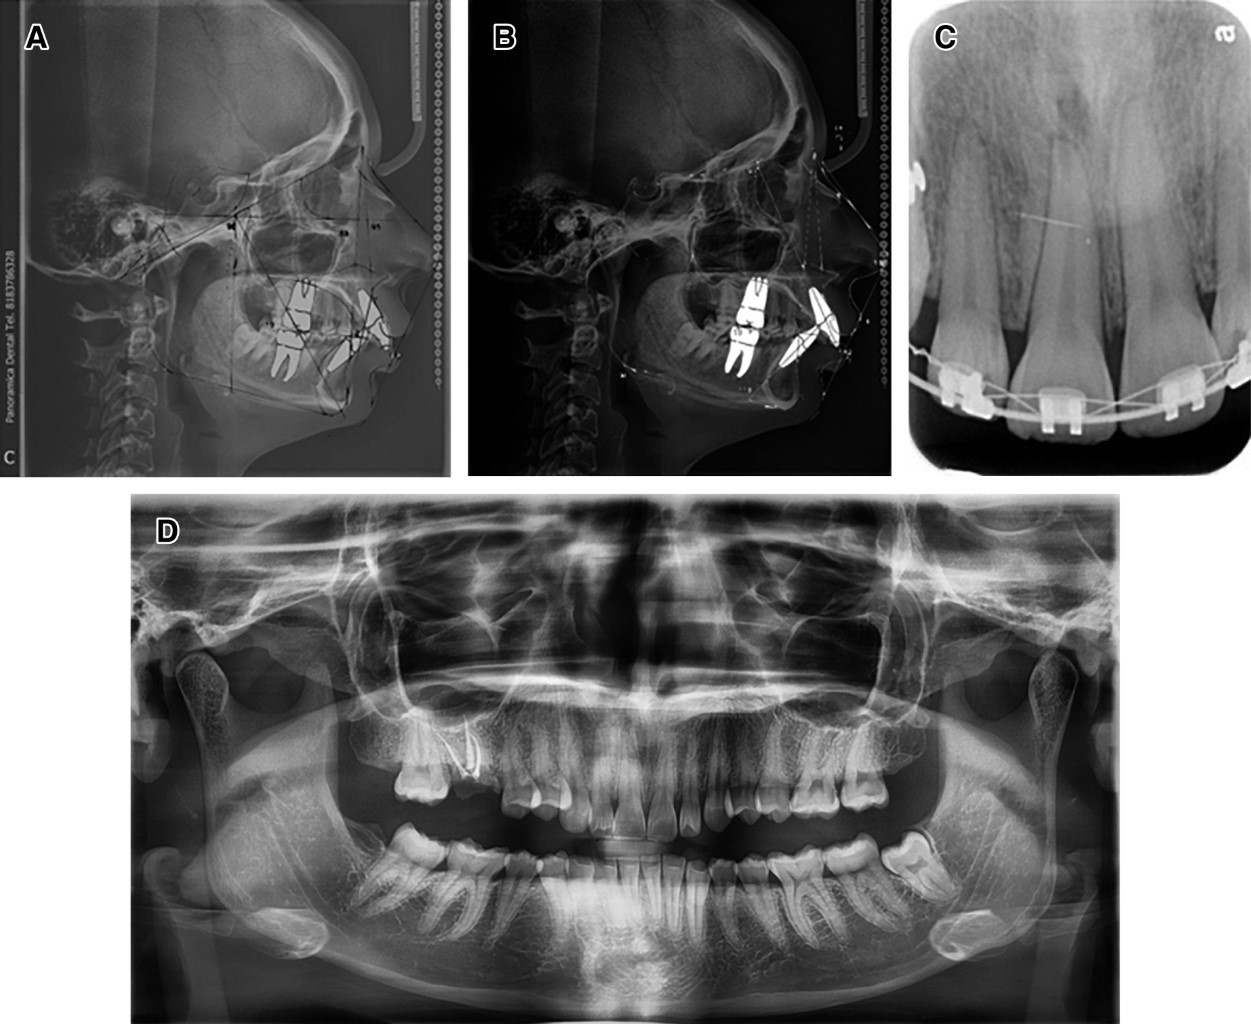

Con los estudios de imagen, se otorga el diagnóstico de erupción pasiva alterada tipo 1 subgrupo B, patrón de crecimiento vertical maxilar, clase II esqueletal (Figura 2).

Figura 2